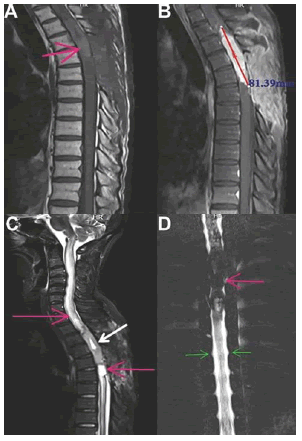

Additionally, whole-spine MRI revealed an intramedullary spinal cord mass located in the thoracic spinal cord between segments T3 and T6. T1-and T2-weighted MRIs of the thoracic spine revealed a sizable intramedullary mass as a hypo-isointense lesion to the spinal cord on T1 and hyperintense on T2, associated with extensive intramedullary swelling from T2 to T6, consisting of an intramedullary cystic area. It was also noted that a significant avid enhancement had developed following gadolinium based contrast agent injection (Figure 1). However, concomitant metastasis was not found in other investigations, such as MRI of the lumbar spine or brain.

neurological-mri

Figure 1. The pre-operation MRI scan of the thoracic spinal cord. Sagittal T1-weighted images show: A solitary (A) hypo-iso intense mass in the intramedullary spinal cord at T3-T6 level (Pink arrow) The lesion (B) showed an avid enhancement with a length of about 8 cm following intravenous gadolinium contrast injection. Sagittal T2-weighted images show: A small (C), sharply well-defined, and hypersignal lesion surrounded by an outer low-signal indicates a cyst due to the degeneration of a tumor cell (white arrow). A fluid-filled cyst (syrinx) within the spinal cord because of a central canal block extending into the cervical cord (Pink arrows). Thoracic myelogram, anteroposterior view: pre-operative myelogram (D) shows a filling defect between T3 and T6 due to an intradural, intramedullary lesion (pink arrows). Exiting nerve roots (green arrows)